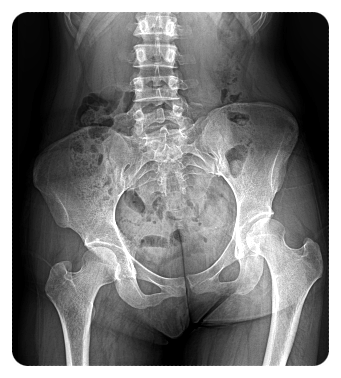

고관절과 무릎, 발은 하나의 축으로 연결돼 있으며, 각자 맡은 역할이 있습니다.

만약 고관절이 안쪽으로 과하게 돌아가는, 이른바 ‘고관절 내회전’ 상태라면 어떤 일이 생길까요?

"이 경우 발 역시

안쪽으로 틀어지기 쉬워집니다."

이렇게 되면 걸을 때 체중이 정상적인 방향이 아닌, 비틀린 상태로 전달됩니다.

그 결과 구조상 가운데에 위치한 무릎이 그 부담을 그대로 떠안게 되죠.

- 고관절의 회전 상태

- 발의 지지 구조

- 무릎 인대의 안정성

이러한 요소들을 함께 살펴보며, 하중이 어떤 방식으로 전달되고 있는지를 먼저 평가합니다.

그래서 저는 무릎 통증을 ‘전체 정렬의 문제’로 보고, 고관절·족부·무릎을 하나의 연결된 축으로 평가합니다.